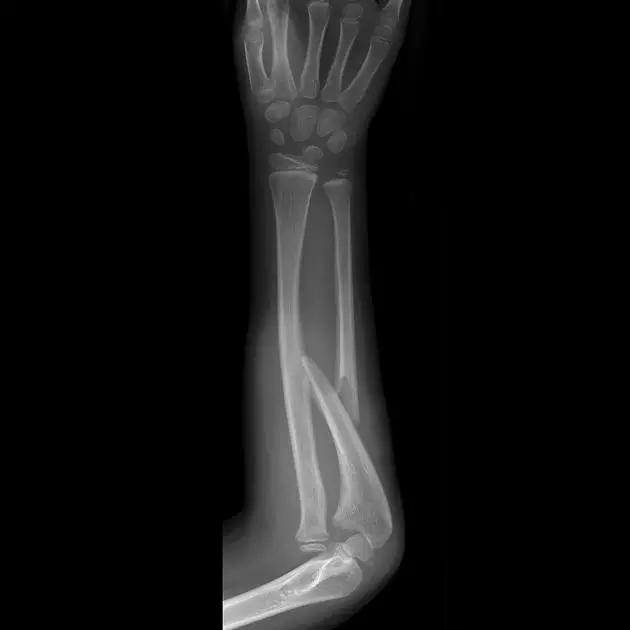

10. Galeazzi 骨折(盖氏骨折)

桡骨干下 1/3 骨折合并尺骨小头脱位。

盖氏骨折正侧位(来源:Orthobullets)